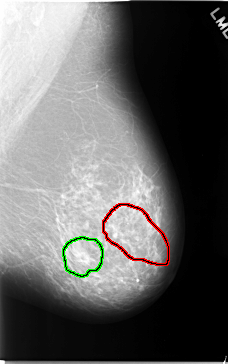

FILE: C_0044_1.LEFT_MLO.OVERLAY TOTAL_ABNORMALITIES 2 ABNORMALITY 1 LESION_TYPE CALCIFICATION TYPE FINE_LINEAR_BRANCHING DISTRIBUTION SEGMENTAL ASSESSMENT 5 SUBTLETY 4 PATHOLOGY MALIGNANT TOTAL_OUTLINES 1 BOUNDARY ABNORMALITY 2 LESION_TYPE MASS SHAPE OVAL MARGINS OBSCURED ASSESSMENT 3 SUBTLETY 5 PATHOLOGY BENIGN TOTAL_OUTLINES 1 BOUNDARY |